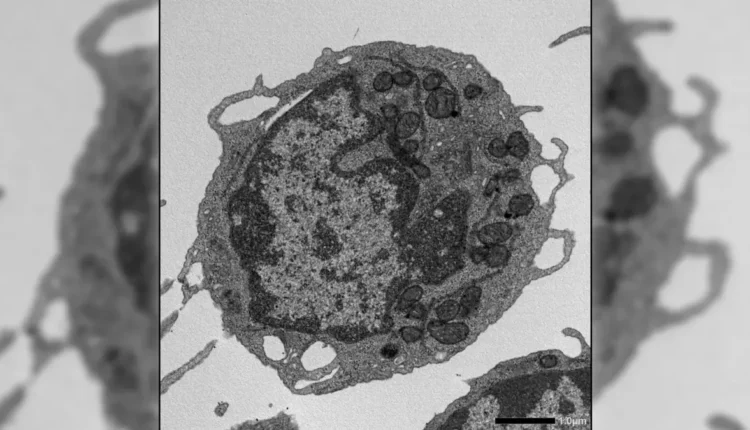

Πρόσθετες τεχνικές παρείχαν βαθύτερες γνώσεις, συμπεριλαμβανομένης της κυτταρομετρίας ροής, της ex vivo επέκτασης, του RNA-seq, του assay for transposase-accessible chromatin-seq, της απεικόνισης υψηλής ανάλυσης, μεταβολικών δοκιμών και λεπτομερών μελετών των μιτοχονδρίων. Μαζί, αυτές οι προσεγγίσεις επέτρεψαν στους ερευνητές να εξετάσουν πώς η MLKL επηρεάζει τα HSCs σε πολλαπλά επίπεδα.

Όταν ενεργοποιήθηκε υπό στρες, η MLKL μετακινήθηκε στιγμιαία στα μιτοχόνδρια, τις δομές που παράγουν ενέργεια μέσα στα κύτταρα. Εκεί, προκάλεσε βλάβη μειώνοντας το δυναμικό της μεμβράνης, αλλοιώνοντας τη μιτοχονδριακή δομή και μειώνοντας την παραγωγή ενέργειας. Αυτές οι επιπτώσεις οδήγησαν σε βασικά χαρακτηριστικά της γήρανσης στα HSCs, συμπεριλαμβανομένης της μειωμένης ικανότητας αυτο-ανανέωσης, της μειωμένης παραγωγής λεμφοειδών κυττάρων και μιας μετατόπισης προς την παραγωγή μυελοειδών κυττάρων.